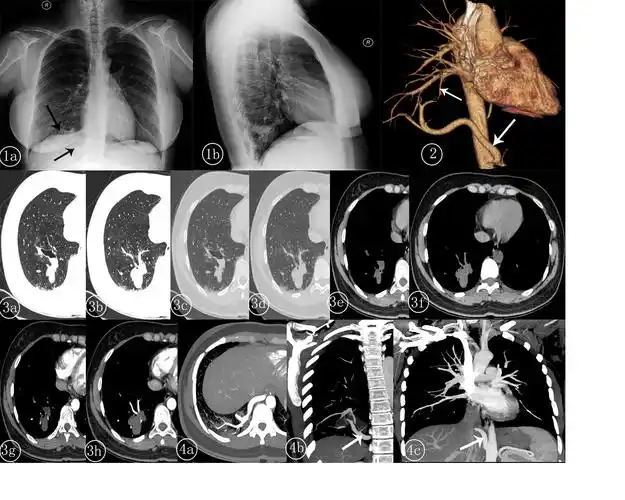

肺隔离症影像表现

右肺下叶肺隔离症一例-中国期刊网

肺隔离症ppt